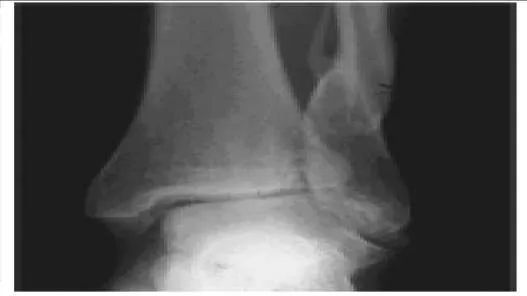

A 56-year-old patient sustained an ankle fracture 3 years ago that was treated with closed reduction and cast immobilization. Since the injury, she has experienced pain upon ambulation and ankle stiffness. On examination, the range of motion of the ankle is 5° of dorsiflexion and 30° of plantarflexion. C repitus with motion is not present, but the patient does experience severe pain. A radiograph is presented (Slide). The recommended procedure to alleviate the patientâ s pain and improve function is:

Correct Answer: Osteotomy of the fibula

The arthritis in this joint is not severe, but there is joint malalignment associated with a short and externally rotated fibula. Joint malalignment is correctable with a lengthening and rotational (internal) osteotomy of the fibula with bone graft. Joint debridement, either open or arthroscopic, is not effective in the management of posttraumatic ankle arthritis. Arthrodesis and arthroplasty are not necessary at this stage.

A 43-year-old construction worker presents for treatment of ankle pain. The patient recounts a fall from a height that caused an ankle fracture 2 years ago. The fracture was treated with closed reduction and cast immobilization for 5 months. He experiences pain upon ambulation and is unable to work. On examination, the range of ankle motion is 5° dorsiflexion and 20° plantarflexion. There is no crepitus with motion, but severe pain is present. A radiograph is presented (Slide 1). The recommended procedure to alleviate pain and improve function is:

Correct Answer: Osteotomy of the tibia and fibula

The arthritis in this joint is not severe, but there is joint malalignment associated with a short and externally rotated fibula and a marked valgus tibiotalar deformity. Although arthrodesis or total ankle replacement may be considered as treatment for some patients, this patient is not a good candidate for these procedures because he does not have severe arthritis. The deformity must be corrected with an osteotomy of the tibia and fibula. Although an opening wedge osteotomy may be considered, a closing wedge procedure is easier to perform and has a higher rate of healing.